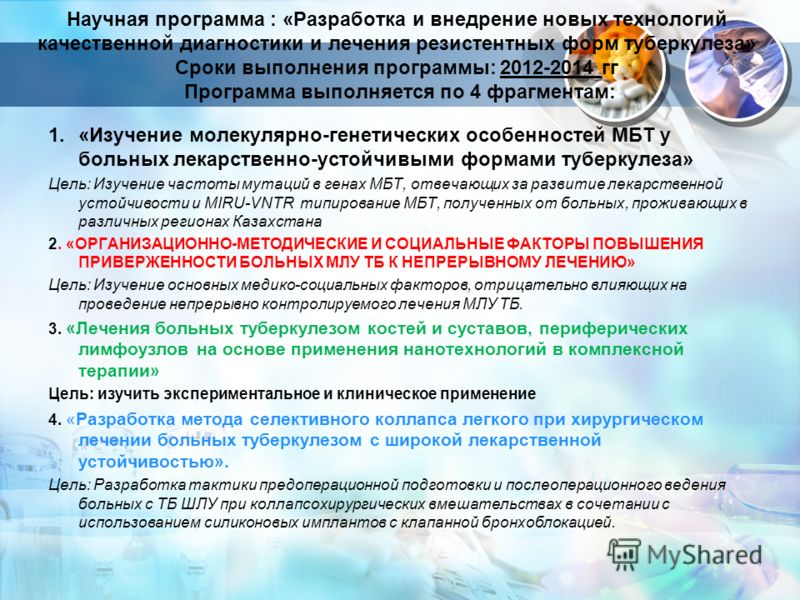

Лечение туберкулеза: Методики химиотерапии

Раздел: Визуальный дайджест